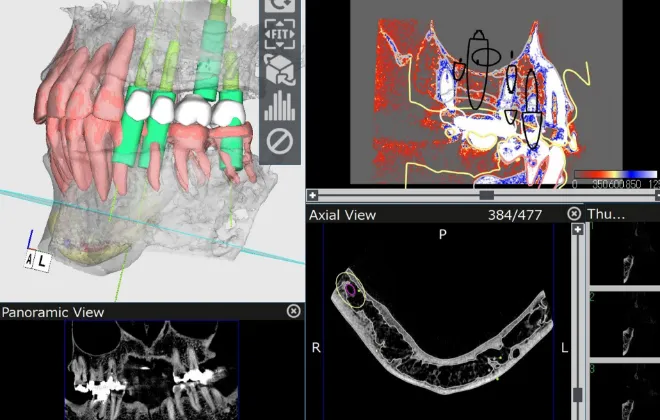

MEDICAL EQUIPMENT

CTスキャンを活用し、

患者様の口腔内を3Dモデル化

えみは総合歯科のインプラント治療は、CTスキャンで口腔内の3Dモデルを作成し、コンピュータシステム「ビオナ」を使用して歯の状態を正確に解析・診断します。

専門医とコンピュータから、精密なインプラント挿入の治療計画を作成します。機械技術と医師の腕が合わさり、患者様の手術への不安や負担を軽くして、手術(インプラント埋め込みの位置・角度)の誤差も従来のものと比べて格段に下がり、ミリ単位の誤差に抑える安全正確な手術になっています。

インプラント治療は体に負担のかかる手術を行うため、綿密な治療計画を立てた上で実行いたします。治療計画は丁寧に患者様にご説明・ご納得いただいた上で進めてまいります。

また、治療はサージカルガイドというインプラントの埋入位置の誤差をなくすためのガイドを利用します。これにより、歯ぐきを最小限もしくは全く切開せずにインプラントの埋入が可能なため手術後の腫れ、痛みが非常に少ないです。

精密検査と治療計画立案

CTスキャンで口腔内の3Dモデルを作成し、歯の状態を正確に解析・診断。精密なインプラント挿入の治療計画を作成します。

当院の対策法

当院では、インプラント手術を行う前の精密検査で通常の歯科用レントゲンだけでなく、CTスキャンの骨の情報とお口の型取りによる歯肉の粘膜の情報をコンピュータ上で統括してシュミレーションを行うことで加えて骨の内部の神経の走行を把握した上で、安全に治療を行なっていますのでご安心ください。

当院の対策法

こちらに関しても、CTスキャンによるシュミレーションを行い位置の把握ができますので、当院ではこのようなことが起こることはありません。

当院の対策法

こちらに関しても、CTスキャンによるシュミレーションを行い位置の把握ができますので、当院ではこのようなことが起こることはありません。